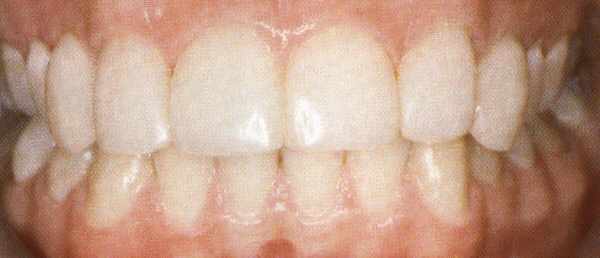

Boventanden vóór de behandeling met composiet.

Dezelfde tanden ná de behandeling met composiet.